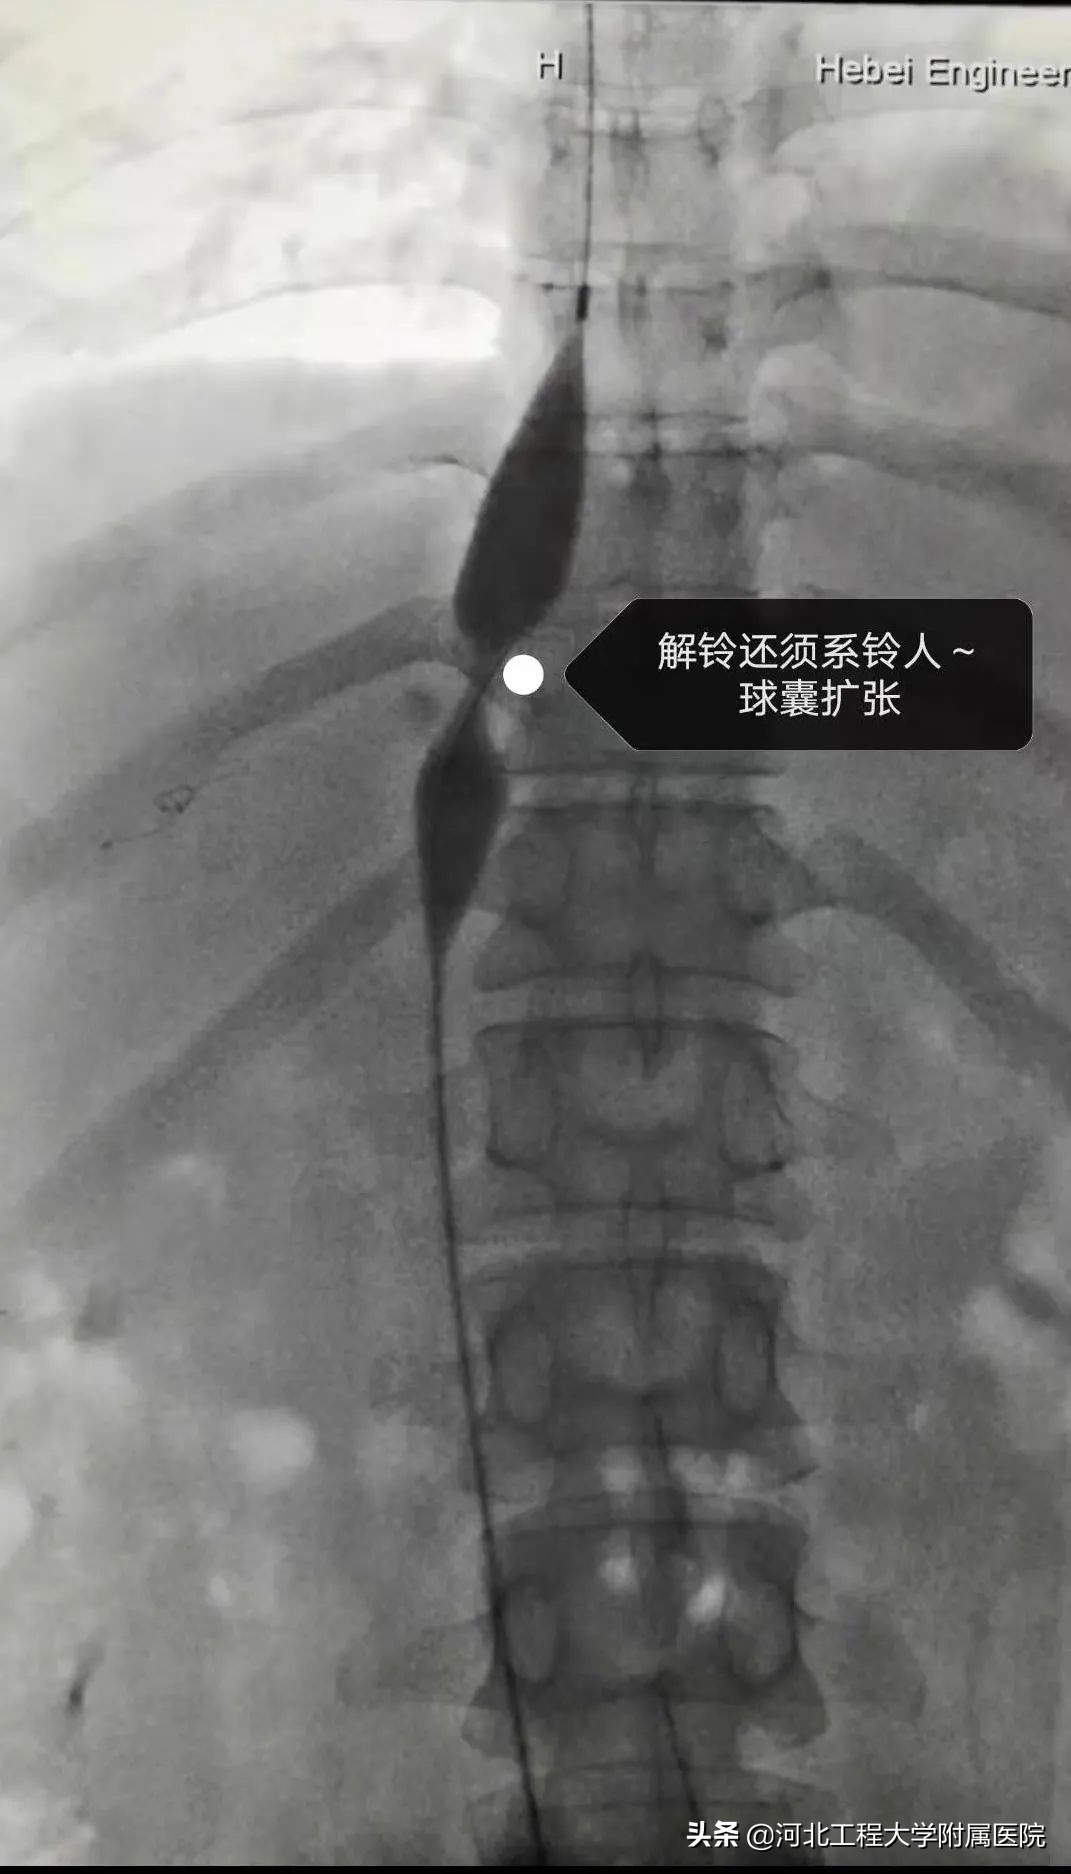

在肿瘤二科主任沈艳峰带领下,在主管医师侯峰岩及微创介入治疗组和导管室的通力合作下,为局麻患者行经皮下腔静脉血管开通成形术,手术顺利完成,术后第2天患者即可下床,术后第5天完全康复,目前已顺利出院。